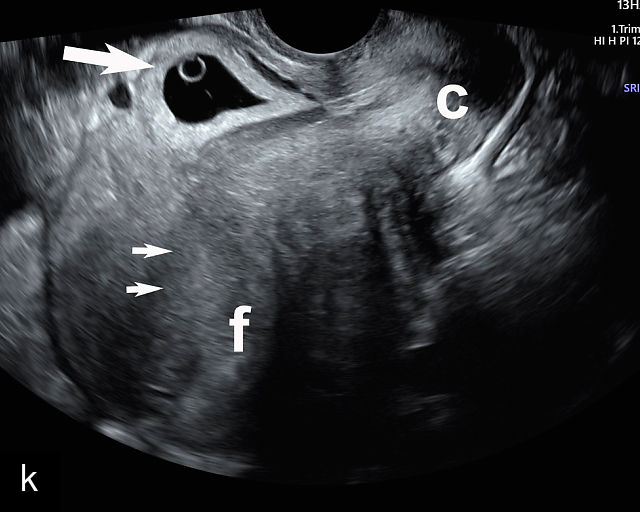

Placenta previa and low-lying placenta. (a) Transabdominal grayscale ultrasound image suspicious for placenta previa. The placenta (PL) appears to overlie the internal cervical os (CX). Note the time stamp: 2:19:37. (b) Transvaginal ultrasound of the same patient taken approximately 50 minutes later. Note the time stamp: 3:10:25. The internal os and the lower placental edge are both clearly seen, and the placenta does not overlie the internal os. Because the lower placental edge is 1.93 cm from the internal os, it will likely resolve by the third trimester. (c) Transabdominal grayscale ultrasound of placenta previa. The placenta (p) covers the cervix, but the cervix, especially the internal os, cannot be visualized due to shadowing. (d) Transabdominal grayscale ultrasound of placenta previa. The placenta (p) covers the cervix (c) but shadowing obscures adequate visualization. The internal os is indicated by the arrow. (e) False-positive image of placenta previa on transabdominal grayscale ultrasound. The bladder (b) is full, pushing the anterior and posterior walls of the lower uterine segment (ls) together making it appear that the placenta (p) overlies the internal os of the cervix. In reality, the line depicted by the arrowheads is where the anterior and posterior walls of the lower segment are in proximity to each other. The cervix is much lower and is obscured by shadowing (c). (f) Transabdominal grayscale ultrasound image of placenta previa. The placenta (p) covers the cervix (c), but the cervix, especially the internal os, cannot be visualized due to shadowing. b, bladder. (g) Transvaginal grayscale ultrasound image of placenta previa. The placenta (p) completely covers the internal os (arrow) of the cervix (c). The internal os can be seen clearly. h, fetal head. (h) Transvaginal grayscale ultrasound image of posterior low-lying placenta (p). The lower placental edge is clearly seen and is 1.56 cm from the internal os (arrow) of the cervix (c). The placental edge and the internal os are clearly seen. h, fetal head. (i) Transvaginal grayscale ultrasound image of a posterior placenta previa (p). The internal cervical os is clearly seen (arrow). c, cervix. (j) Transvaginal grayscale ultrasound image of an anterior placenta previa (p). The internal cervical os is clearly seen (arrow). c, cervix; h, fetal head. (k) Transvaginal grayscale ultrasound image of a posterior placenta that was thought to be low-lying on transabdominal sonography but could not be adequately assessed. This examination clearly shows the lower edge of the placenta (p) to be 2.18 cm from the internal os (arrow) of the cervix, firmly establishing that the placenta is not low-lying and allowing the patient to undergo labor safely and deliver vaginally. c, cervix. (l) Transvaginal grayscale ultrasound image of placenta previa. The placenta (p) completely covers the internal os (arrow) of the cervix (c). The internal os can be seen clearly.

Most cases of placenta previa will be suspected prenatally by transabdominal ultrasound.49 However, this approach has several limitations and may be inaccurate.72,73,74 because the relationship between the placenta and the internal cervical os may be difficult to assess by transabdominal ultrasound.72,73,74 The bladder may be full, pushing the anterior and posterior walls of the lower uterine segment together, falsely creating the impression of a placenta previa (Figure 5e).61 There may be considerable shadowing, including by the fetal presenting part, which may limit the accuracy of transabdominal ultrasound (Figure 5d,f).75 Posterior placentas may be more difficult to assess.

Transvaginal ultrasound overcomes these limitations (Figure 5g–l).72,73,74,76 The probe is inserted into the vagina and therefore is closer to the region of interest.51,61 In addition, transvaginal transducers have higher frequencies and superior resolution compared to transabdominal transducers. Transvaginal ultrasound is safe and is not associated with increased bleeding.72,73,74,75,76 As such, transvaginal ultrasound should be the imaging modality of choice whenever there is suspicion of placenta previa.49,67,77